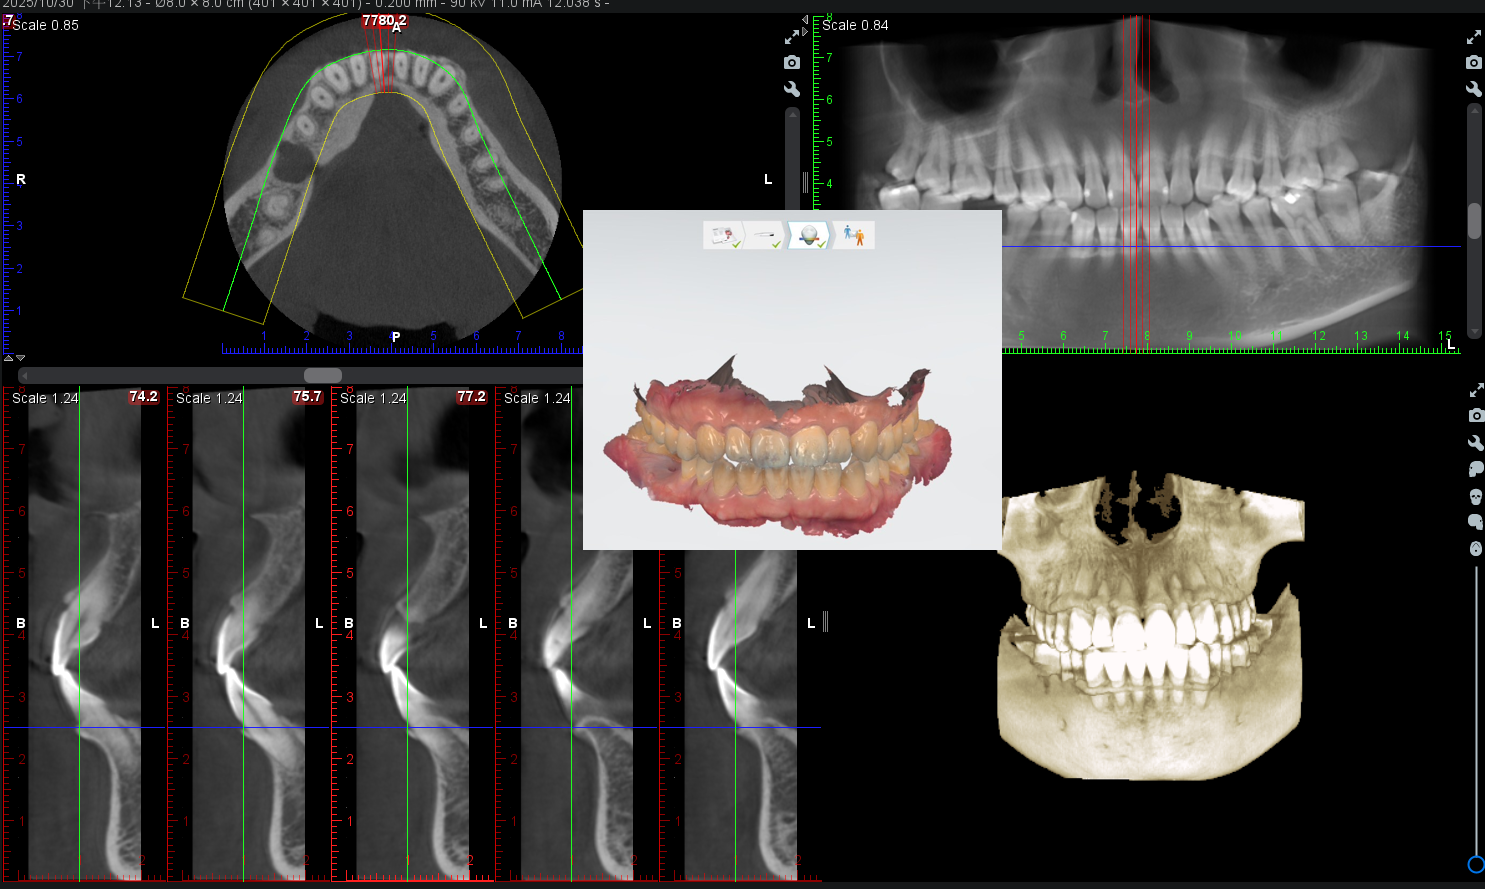

全面檢查牙齒與骨頭狀況,利用X光影像及口內掃描確認牙齒及牙周狀況。